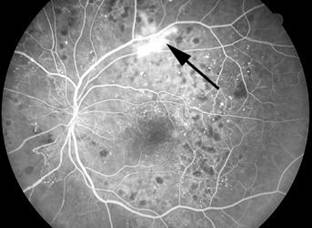

Hiperfloresans ise floresein sızıntısı, boyanması, göllenmesi veya aktarım defektleri ve otofloresans sebebiyle gerçekleşir. Florosein sızıntısı, koroid neovaskülarizasyonundaki veya diyabetik neovaskülarizasyondaki gibi yetersiz kan damarlarından veya koroidden floresein sızıntısını artık bloke edemeyen hastalıklı bir retina pigment epitelinden gelebilir. FA’da sızıntı alanları kademeli genişleme ve marjinlerinde bulanıklıkla kendini gösterir. Bu durum boyanan yapılardan farklıdır. Boyanmada anjiogram boyunca artan floresans meydana gelir ancak marjinler belirgin kalmaya devam eder. Optik sinir başı ve sklera gibi normal yapılar boyanır ama drusen ve diskiform skarı gibi patolojiler de floreseinle boyanır. Göllenme, floreseinin sıvı dolu bir boşluğu gitgide doldurmasıyla gerçekleşir. Aktarım veya pencere defekti ise normalde floresansı bloke eden bir katmanın yokluğunda oluşur. Bu en yaygın olarak RPE olmadığında ve parlak koroid floresansı FA’da erken gözüktüğünde meydana gelir. Floresansın yoğunluğu solmaya başlar ve marjinler belirgin kalmaya devam eder. Otofloresans ise, floresein boyası enjekte edilmeden önce optik sinir başı druseni ve lipofusin gibi yapılar normalde floresan ışığı yaydığında görülebilir. Bazı özel donanımlı tarayıcı lazer oftalmoskoplarında ve fundus kameralarda, RPE tabakasının durumunu belgelemek için lipofusin floresansı kullanılabilir.